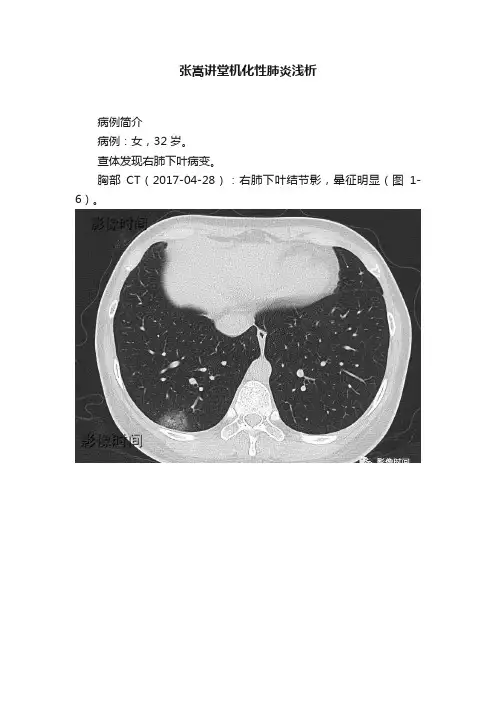

张嵩讲堂机化性肺炎浅析病例简介病例:女,32 岁。

查体发现右肺下叶病变。

胸部CT(2017-04-28):右肺下叶结节影,晕征明显(图1-6)。